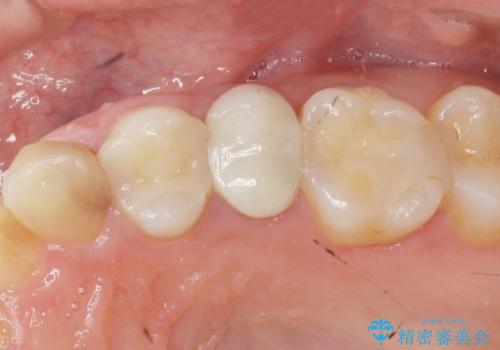

当初、歯ぐきよりも深い虫歯の存在や、歯のポジションに問題がありましたがマルチブラケットを用いた部分矯正で行うことで歯の挺出同時に適切な位置へと歯を移動させ、歯周環境を整えたセラミック治療を行うことができました。